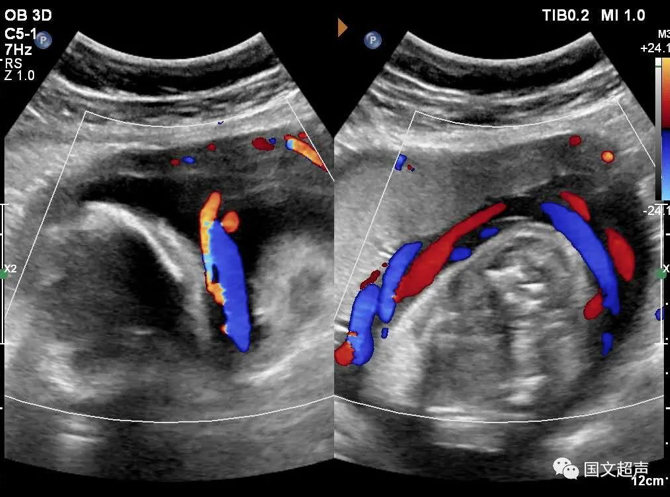

四.關(guān)于臍帶繞頸

臍帶有補(bǔ)償性伸展,纏繞松弛對(duì)胎兒影響不大,但如果纏繞過(guò)緊可影響胎兒血供,有造成胎心率改變、胎兒缺氧、窒息甚至胎死宮內(nèi)的風(fēng)險(xiǎn)。

實(shí)際上影響胎兒預(yù)后的主要因素不在于繞頸的周數(shù),而在于除去繞頸所剩的臍帶長(zhǎng)度。如果孕媽媽只繞頸一周但臍帶相對(duì)過(guò)短,仍可造成不良結(jié)局。

臍帶繞頸的孩子很多,但發(fā)生不良結(jié)局的確占少數(shù),所以不必過(guò)度擔(dān)心,只要每天的胎動(dòng)正常,沒(méi)有突然的增多和減少,定期復(fù)查即可。